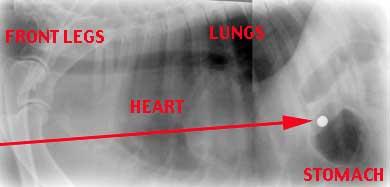

Xrays were taken and the bullet and its path through the dog can clearly be seen (Shown in red). Fortunately, the bullet missed the heart and did little damage to the lungs and liver before ending up in the stomach.

The bullet was surgically removed from the stomach and after a fortnight in hospital in intensive care, she went home to her very worried owners. She took a further two months to fully recover from her injuries (Bullet shown right)